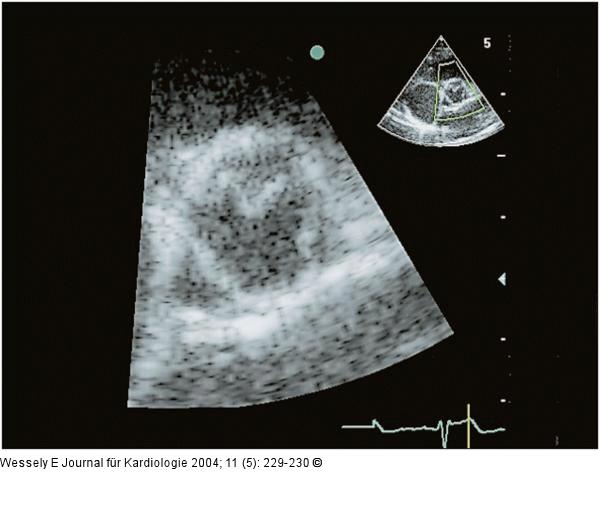

Abbildung 2: Membranöse Subaortenstenose

Parasternaler Querschnitt, Aortenklappe frühsystolisch |